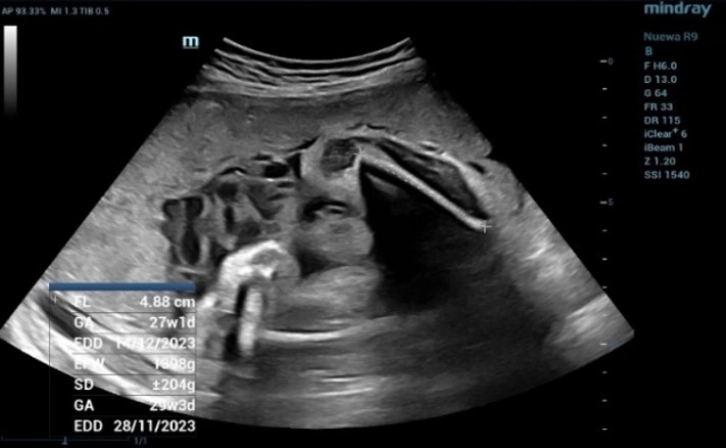

Fetal Biometric Measurements: Femur Length (FL)

Figure 2 Fetal Biometric Measurements: Femur Length (FL). FL is a basic biometric parameter to assess fetal size

The measurement of Biparietal Diameter (BPD) (Figure 1) and Femur Length (FL) (Figure 2) demonstrated a close approximation to the actual gestational age. However, when assessing the Abdominal circumference (AC), it was observed that the measured gestational age exceeded the actual gestational age due to the presence of fluid accumulation around the fetal abdomen (Figure 3).